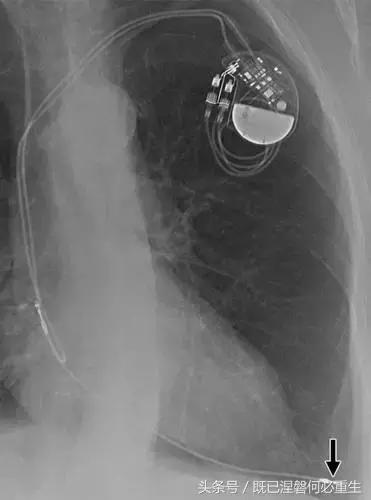

用于将导线的近端部分固定到胸壁的导线固定件可以模拟损伤。扎带是通常位于锁骨和发生器之间并且可以压接引线的套囊(图8A和8B)。熟悉这种外观和通常的射线透射束缚的位置可以防止错误报告磨损的线索。

图。 8A在两个不同患者中电极断裂的电极结合物的实例。

图。 8B在两个不同患者中电极断裂的电极结合物的实例。